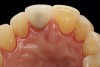

The patient was postoperatively evaluated at 1-, 2-, 4-, 8-, and 12-week recall appointments. The sutures were removed at the 2-week appointment, and the patient was instructed to rinse twice daily and avoid brushing the anterior maxilla. Prior to provisionalization of the implant, the site was allowed to heal for 6 months, during which time the patient was temporized with another Maryland bridge. At the 6-month recall appointment, full mouth periodontal maintenance was completed, and an implant-retained acrylic provisional restoration was placed (Figure 23 through Figure 25). An acrylic provisional restoration allows for soft-tissue attachment while preventing apical migration of the gingival margin. After a 3-month provisionalization period, the final prosthesis was delivered (Figure 26 through Figure 29), and the patient was scheduled for ongoing 3-month recall appointments for periodontal maintenance.

(26.) Facial and occlusal views of the soft-tissue contour achieved after 3 months of provisionalization. The tissue is thick with a harmonious gingival contour and zenith position.

Figure 26

(27.) Facial and occlusal views of the soft-tissue contour achieved after 3 months of provisionalization. The tissue is thick with a harmonious gingival contour and zenith position.

Figure 27